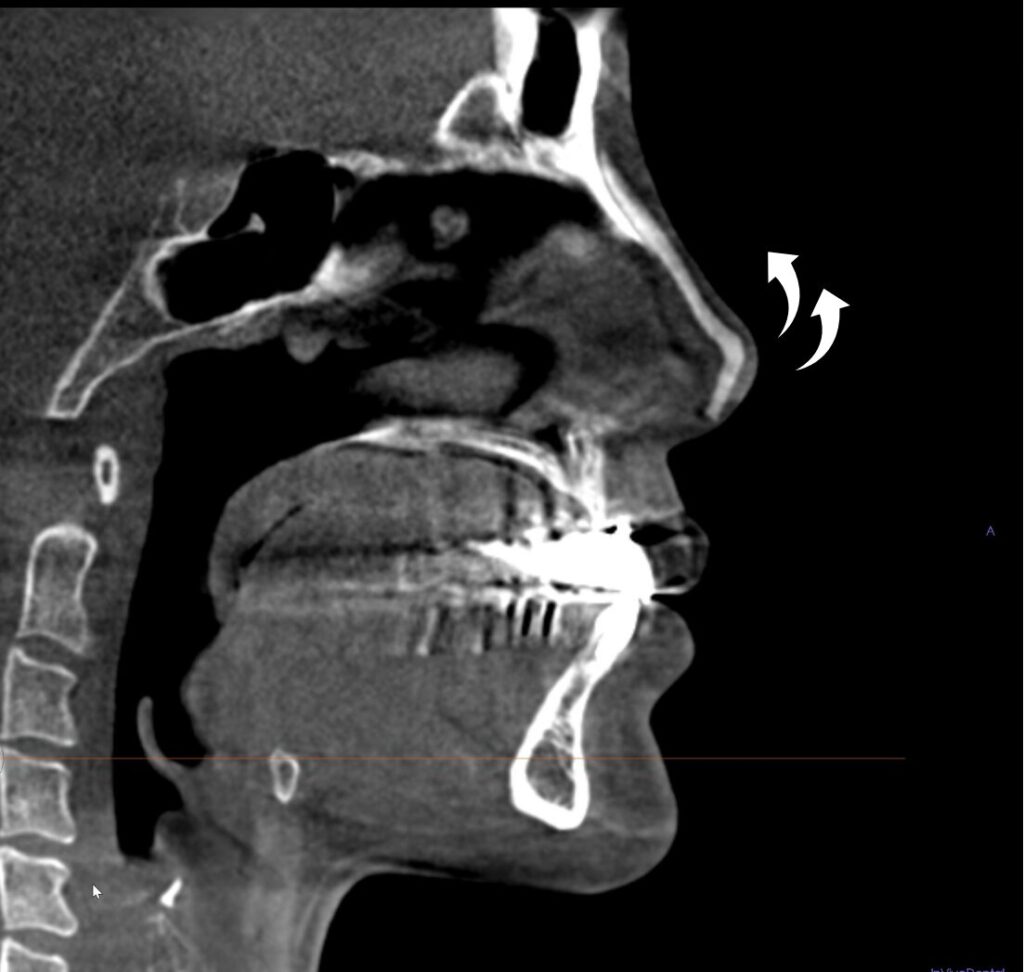

CT画像で読み解く“変形のサイン”

鼻の内部で何が起きているかは、外からの見た目だけでは分かりません。

そこで非常に役立つのが CT画像(断層画像) です。内部構造が立体的に見えるため、プロテーゼの位置、軟骨の変形、被膜の状態、異物の有無を正確に評価できます。

ここに示すCTは、L型プロテーゼが挿入されている典型的な例です。

1. L型プロテーゼが鼻先まで深く入り込んでいる

鼻背から鼻先まで、硬いシリコンの影が連続しており、本来は動くべき軟骨の領域に、硬いシリコンが食い込んでいる状態で、これが鼻先を押し上げる「きっかけ」になります。

2. プロテーゼ先端が皮膚のすぐ下にある

鼻先の皮膚直下にプロテーゼの先端があり、皮膚菲薄化(皮膚が薄くなる)を示唆します。放置すると赤みや露出のリスクがあります。

3. 被膜(カプセル)の拘縮が強い

プロテーゼの輪郭が非常にクリアで、周囲の軟部組織が硬くまとわりつく像。長期間の“被膜拘縮”が疑われます。

4. 鼻柱・鼻中隔が押し上げられている

長年プロテーゼに押されたことで、軟骨が上方に変位しているのが分かります。

5. アクアミド(非吸収性フィラー)の残存を疑う影

一定の層に広がる不均一な“もやっとした陰影”があり、アクアミドの像と一致します。炎症や拘縮、骨吸収の原因になります。